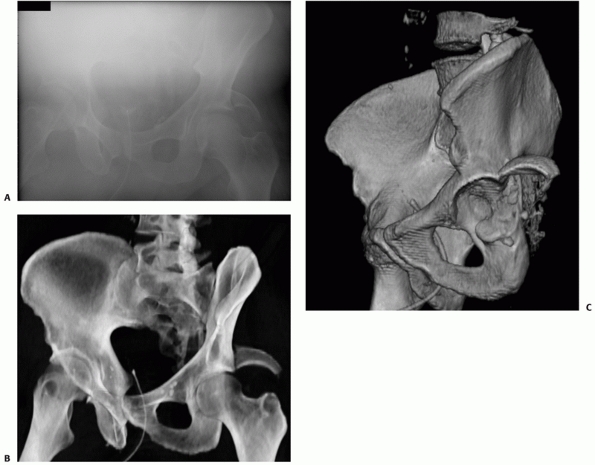

![]() |

FIGURE 45-5 An 18-year-old 390-pound man (A) was involved in a motor vehicle accident. Anteroposterior radiograph (B) of the hip and selected two-dimensional computed tomography section (C) show a T-type fracture of the acetabulum and an ipsilateral fracture of the femoral shaft (D). Retrograde nailing was used to stabilize the femur (E) followed by acetabular fixation 2 days later (F) using the Kocher-Langenbeck approach. (Copyright Berton R. Moed, MD.)